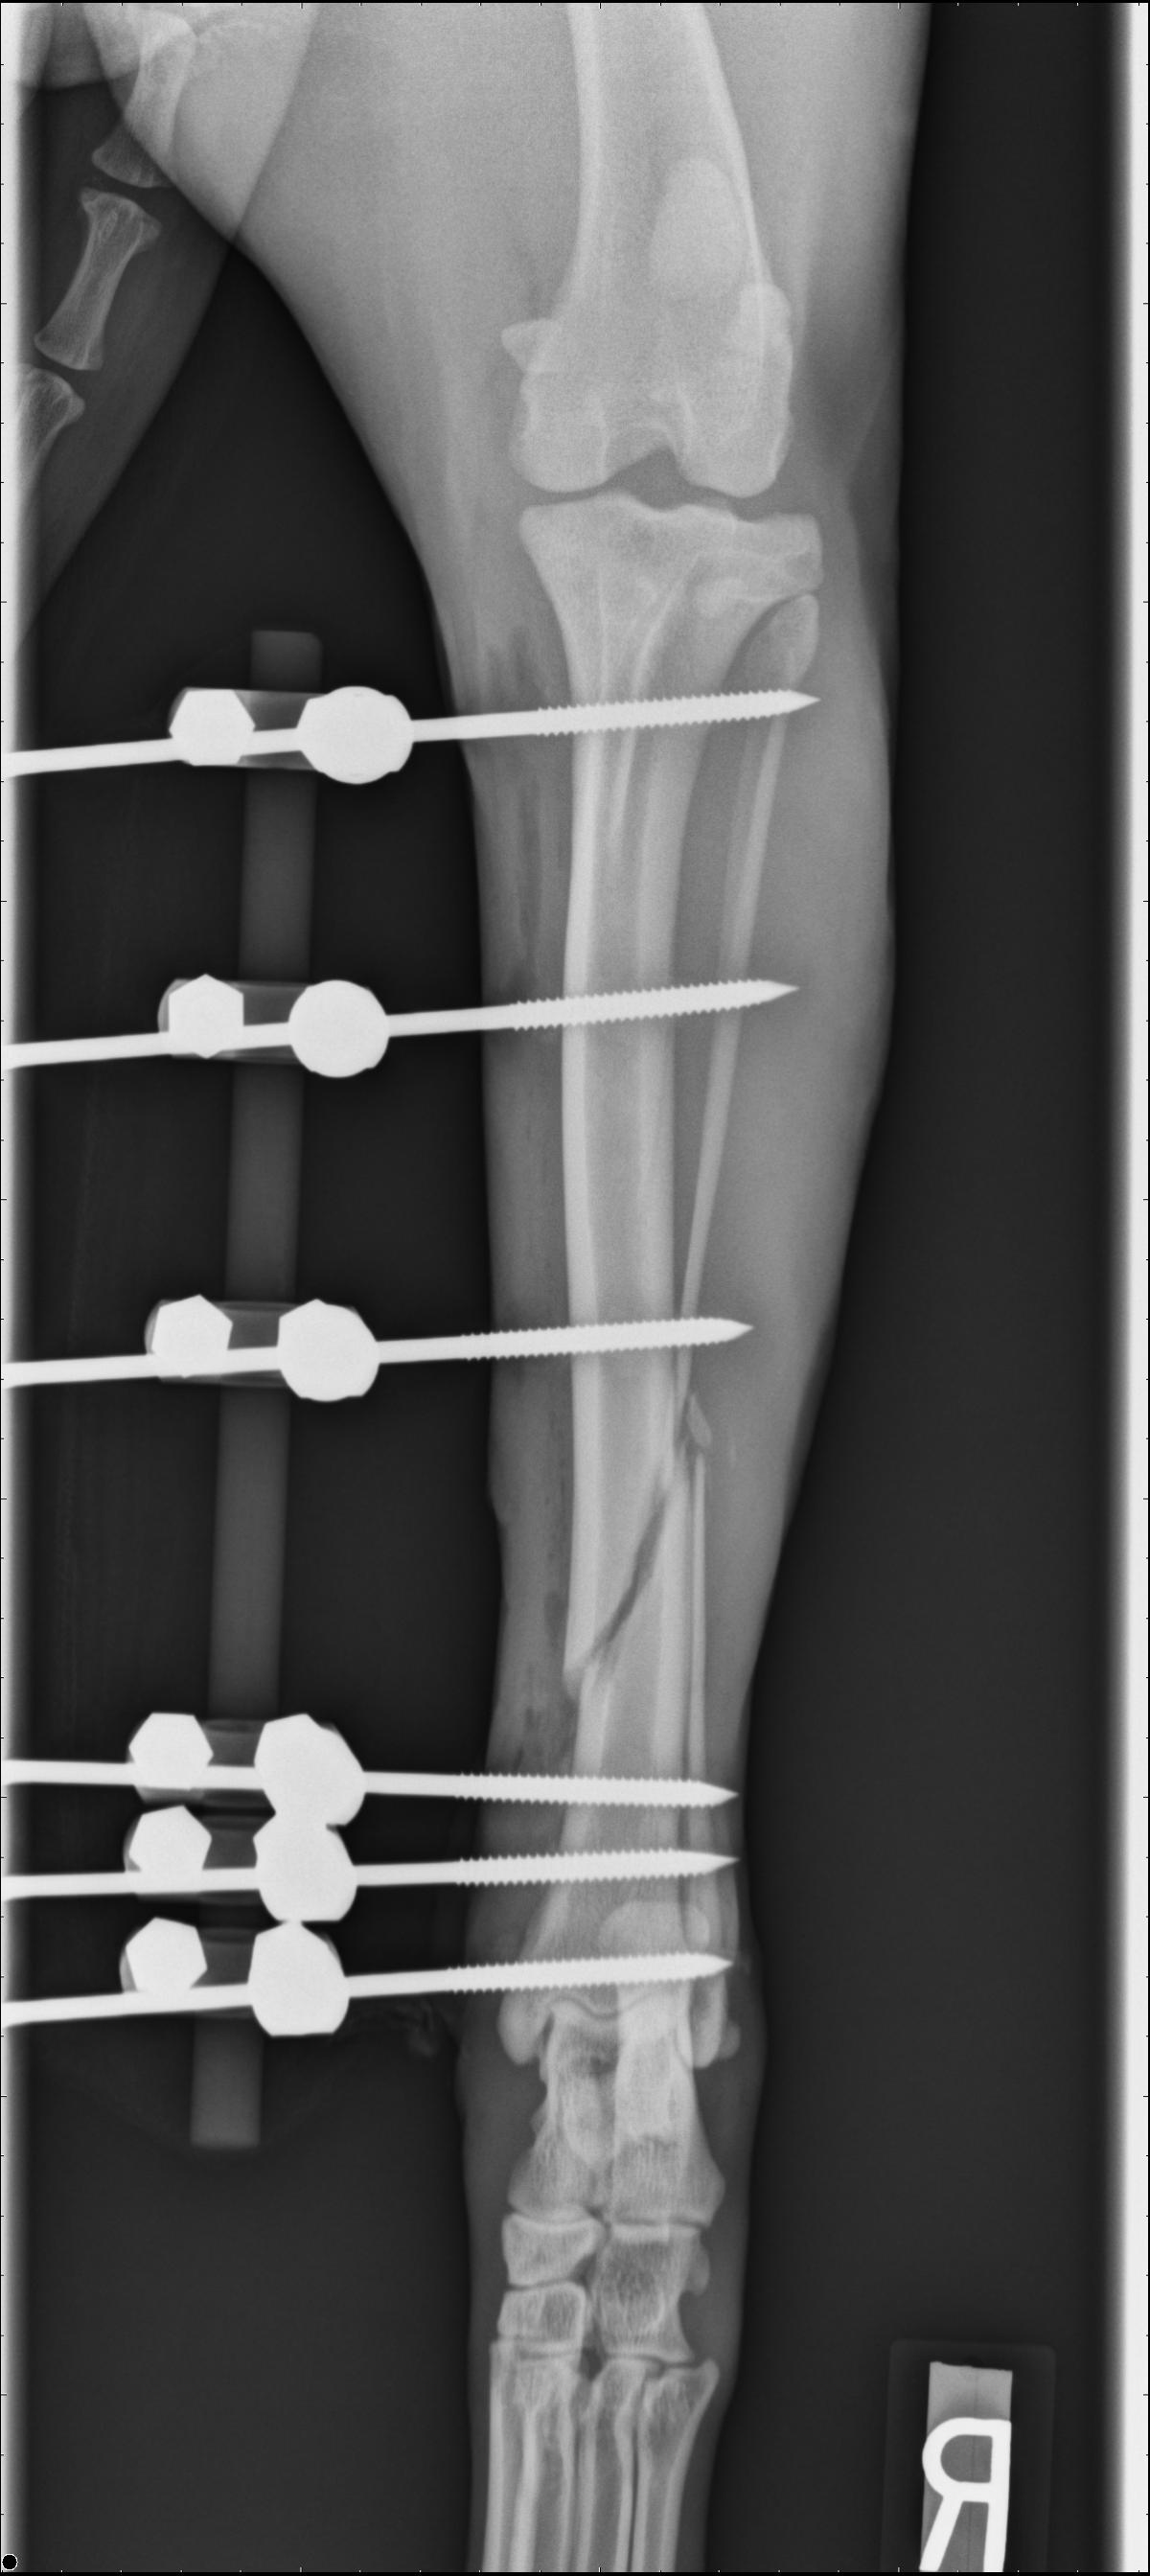

Patient with a Sliding Humeral Osteotomy (SHO).